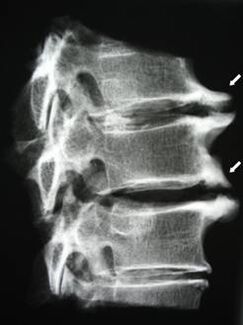

En las etapas iniciales, la osteocondrosis se detecta mediante resonancia magnética.. Posteriormente, la patología se puede diagnosticar mediante radiografía. En las radiografías de la columna cervical, se nota una disminución en la distancia entre las vértebras, cambios patológicos en las articulaciones facetarias y osteofitosis.